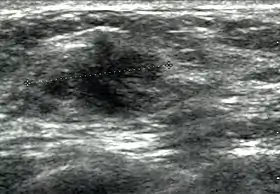

Breast ultrasound is a medical imaging technique that uses medical ultrasonography to perform imaging of the breast. It can be performed for either diagnostic or screening purposes[1] and can be used with or without a mammogram.[2] In particular, breast ultrasound may be useful for younger women who have denser fibrous breast tissue that may make mammograms more challenging to interpret.[3]

Elastography is a type of ultrasound examination that measures tissue stiffness and can be used to detect tumours.[6] Breast ultrasound is also used to perform fine-needle aspiration biopsy and ultrasound-guided fine-needle aspiration of breast abscesses.[7]